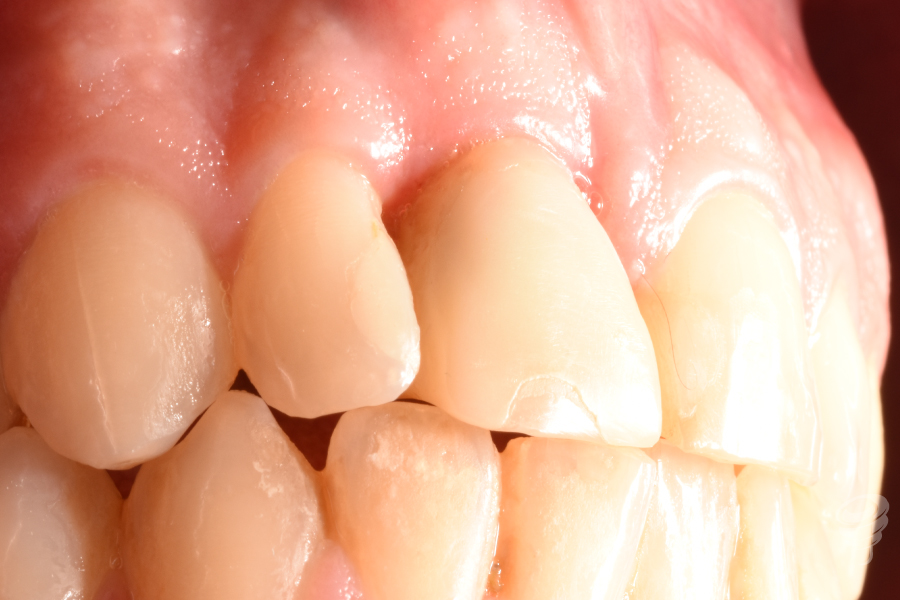

Figura 1